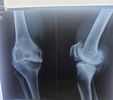

Who is a Fracture treatment specialist in Kolkata?

For Fracture treatment in Kolkata, you need to see an orthopaedic surgeon. They are the ones who can look at your bone injuries and figure out how bad the fracture is.